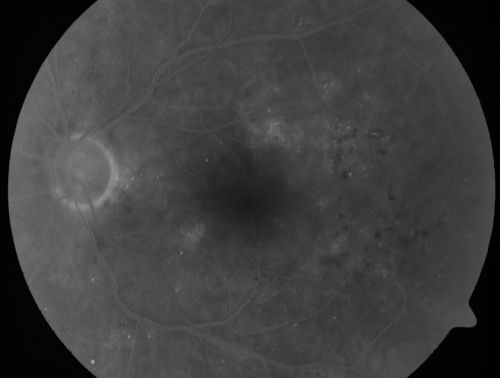

Clinically Significant Diabetic Macular Edema both Eyes with Exudates

56-year-old woman with diabetes for twelve years. She has noticed blurring of the vision in the right eye for about six months. OD is 20/70, OS is 20/25.